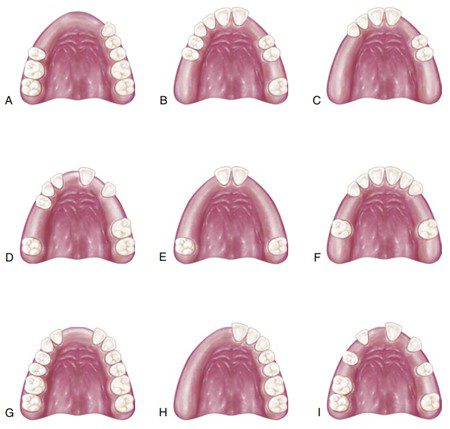

Kennedy đã chia tất cả các trường hợp mất răng bán phần thành bốn loại cơ bản. Những vị trí mất răng nằm ngoài 4 phân loại này sẽ được xếp vào “biến thể” (Hình 3.1.8.).

- Loại I: Vùng mất răng tận cùng hai bên, nằm phía sau các răng tự nhiên còn lại. Yên răng giả phục hồi những vùng mất răng như vậy được gọi là ‘yên mở rộng về phía xa’.

- Loại II: Vùng mất răng tận cùng một bên.

- Loại III: Vùng mất răng một bên với các răng thật còn lại ở cả phía trước và phía sau. Yên răng giả phục hồi loại vùng mất răng này được gọi là ‘yên giới hạn’.

- Loại IV: Một vùng mất răng đơn lẻ nhưng hai bên (vượt qua đường giữa) nằm phía trước các răng tự nhiên còn lại.

Một trong những ưu điểm chính của phân loại Kennedy là cho phép quan sát ngay cung hàm mất răng bán phần và dễ dàng phân biệt giữa phục hình được nâng đỡ bởi răng với phục hình được nâng đỡ bởi răng và mô. Bác sĩ có thể dễ dàng liên tưởng thiết kế sẽ được sử dụng trong hàm khung bán phần cơ bản ngay khi nhìn thấy kiểu mất răng.